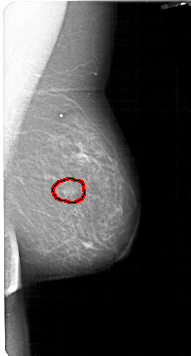

A_1435_1.LEFT_MLO

LEFT_MLO LINES 4936 PIXELS_PER_LINE 2746 BITS_PER_PIXEL 12 RESOLUTION 43.5 OVERLAY

FILE: A_1435_1.LEFT_MLO.OVERLAY

TOTAL_ABNORMALITIES 1

ABNORMALITY 1

LESION_TYPE MASS SHAPE OVAL MARGINS ILL_DEFINED

ASSESSMENT 4

SUBTLETY 3

PATHOLOGY BENIGN

TOTAL_OUTLINES 1

BOUNDARY